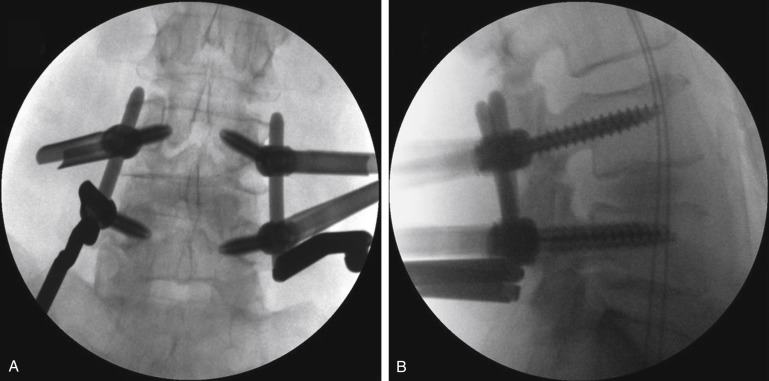

Endoscopic Lumbar Interbody Fusion Neupsy Key Applications of the endoscope are prevalent in a variety of procedures from the cervical to lumbar spine. this review focuses specifically on endoscopic lumbar interbody fusion (lif) and details the specific indications, techniques, outcomes, and complications associated with these procedures. This paper critically reviews current evidence on the safety, efficacy, and advantages of endoscopic lumbar spinal interbody fusion, examining whether it could indeed supersede existing mainstream techniques. The indications of endoscopic spine surgery have shifted from simple discectomies, decompressions to lumbar interbody fusions. in recent years promising results are reported for grade one or two level lumbar and thoracic fusions. We present two illustrative cases of endoscopic transforaminal lumbar interbody fusion with a comprehensive literature review of the different approaches to endoscopic lif procedures. Advancements in both surgical instrumentation and full endoscopic spine techniques have resulted in positive clinical outcomes in the treatment of cervical, thoracic, and lumbar spine pathologies. These include lumbar disc herniations, spinal stenosis, and lumbar spinal fusion. this review provides comprehensive, up to date analyses of the 2 main approaches—uniportal and biportal endoscopy—utilized for discectomy, foraminotomy, laminectomy, and interbody fusion.

Lumbar Spinal Fusion Process By Nathan Warwick At Coroflot The indications of endoscopic spine surgery have shifted from simple discectomies, decompressions to lumbar interbody fusions. in recent years promising results are reported for grade one or two level lumbar and thoracic fusions. We present two illustrative cases of endoscopic transforaminal lumbar interbody fusion with a comprehensive literature review of the different approaches to endoscopic lif procedures. Advancements in both surgical instrumentation and full endoscopic spine techniques have resulted in positive clinical outcomes in the treatment of cervical, thoracic, and lumbar spine pathologies. These include lumbar disc herniations, spinal stenosis, and lumbar spinal fusion. this review provides comprehensive, up to date analyses of the 2 main approaches—uniportal and biportal endoscopy—utilized for discectomy, foraminotomy, laminectomy, and interbody fusion.